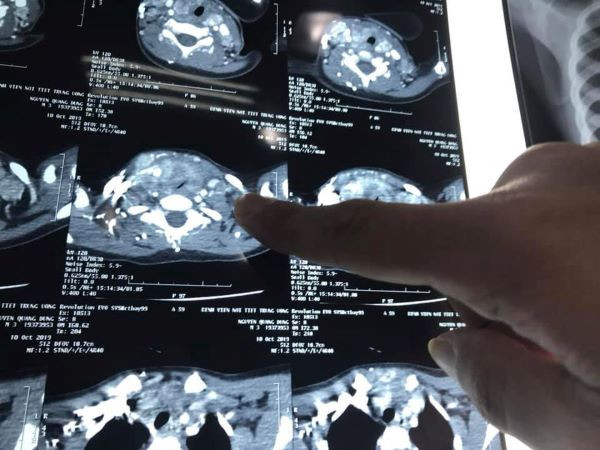

Tại đây, sau khi thực hiện các chỉ định cận lâm sàng, bé D. được chẩn đoán ung thư tuyến giáp với mức độ di căn nhiều hạch cổ 2 bên. Khối u đã phát triển lớn chèn ép khí quản gây khó thở.

| Hình ảnh phim chụp (BVCC). |

Ca phẫu thuật kéo dài hơn 2 giờ đồng hồ do trong quá trình gây mê và phẫu thuật đều gặp rất nhiều khó khăn. Do mức độ di căn lan rộng vào cả dây thần kinh quặn ngược, tĩnh mạch cảnh và khí quản gây đè bẹp khí quản khiến cho việc đặt nội khí quản trong quá trình gây mê, quá trình bóc tách, nạo các nhóm hạch ở vùng cổ hết sức khó khăn.

Cũng theo PGS Lương, ngay trong quá trình phẫu thuật, hạch di căn của bé D. đã được đem đi thực hiện cắt lạnh tế bào và cho kết quả ung thư tuyến giáp thể tủy. Đây được coi là thể ít gặp đối với những bệnh nhân nhỏ tuổi trong ung thư tuyến giáp và chỉ có khoảng 5% trường hợp mắc phải.